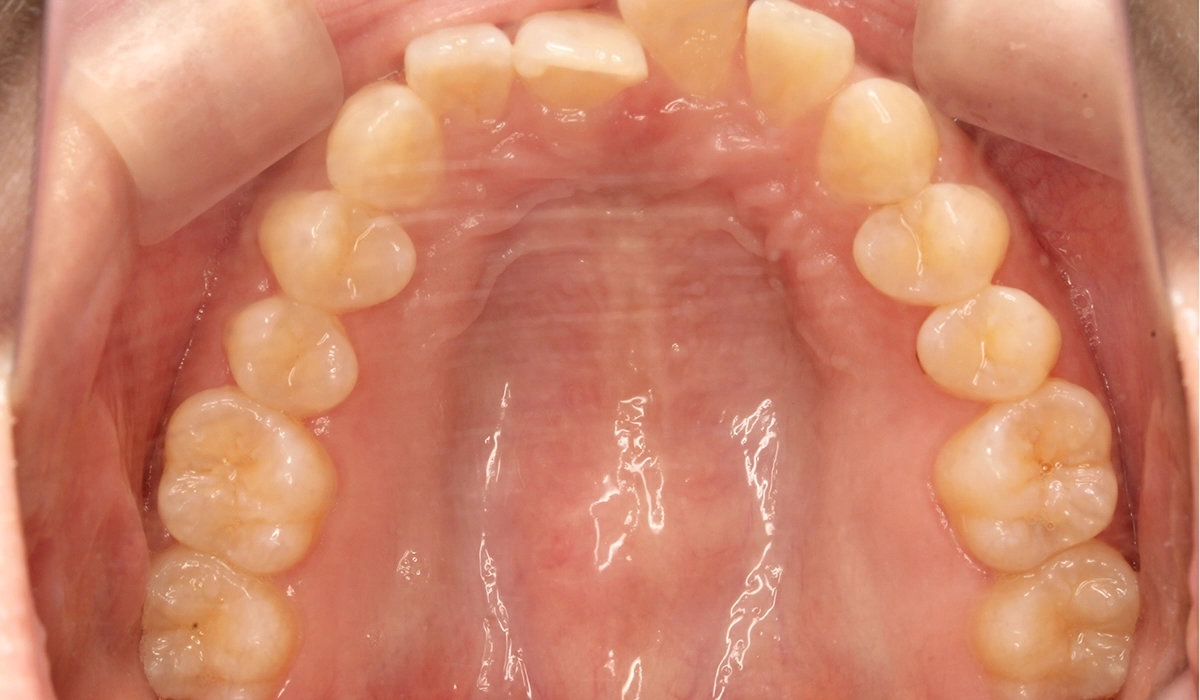

術前:上顎

術後:上顎